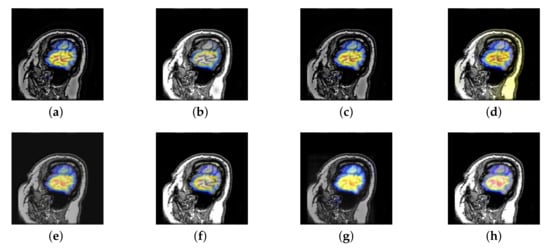

4.3. The Fusion of MRI-FDG

Fludeoxyglucose (FDG) image in cancer diagnosis plays an important role; at the same time, it provides the functional information that can predict a pathological reaction to certain types of cancer treatment. As a kind of PET image, FDG image has some features of PET image, such as texture analysis [54] and shape analysis [55], may also provide additional knowledge associated with the treatment outcome. However, FDG image has no structural information, which is its biggest defect. Therefore, the fusion of MRI and FDG can give doctors a great help in the process of cancer diagnosis.

In this section, all FDG images are derived from the normal human brain, but the angle is chosen differently in Figure 24. In Figure 25, Figure 26, Figure 27 and Figure 28, we find that the color information obtained by the image fusion method based on NSCT, DTCWT, and LPSR is better preserved, but the structure information is lost more. The fusion image based on GFF, IGM, and FusionCNN method retains the complete structure information in the MRI image, but the color obtained from the FDG image is distorted. The image color information obtained by DDcGAN fusion method is too bright, resulting in unclear color area details and low contrast of color region. In contrast, the image obtained by our algorithm has moderate brightness of color information, complete structure information, and complete biological detail information.

Figure 25.

Fused medical images obtained by different algorithms (Figure 24a,b): (a) DTCWT, (b) GFF, (c) NSCT, (d) LPSR, (e) IGM, (f) FusionCNN, (g) DDcGAN, and (h) FusionNet.

Figure 26.

Fused medical images obtained by different algorithms (Figure 24c,d): (a) DTCWT, (b) GFF, (c) NSCT, (d) LPSR, (e) IGM, (f) FusionCNN, (g) DDcGAN, and (h) FusionNet.

Figure 27.

Fused medical images obtained by different algorithms (Figure 24e,f): (a) DTCWT, (b) GFF, (c) NSCT, (d) LPSR, (e) IGM, (f) FusionCNN, (g) DDcGAN, and (h) FusionNet.

Figure 28.

Fused medical images obtained by different algorithms (Figure 24g,h): (a) DTCWT, (b) GFF, (c) NSCT, (d) LPSR, (e) IGM, (f) FusionCNN, (g) DDcGAN, and (h) FusionNet.